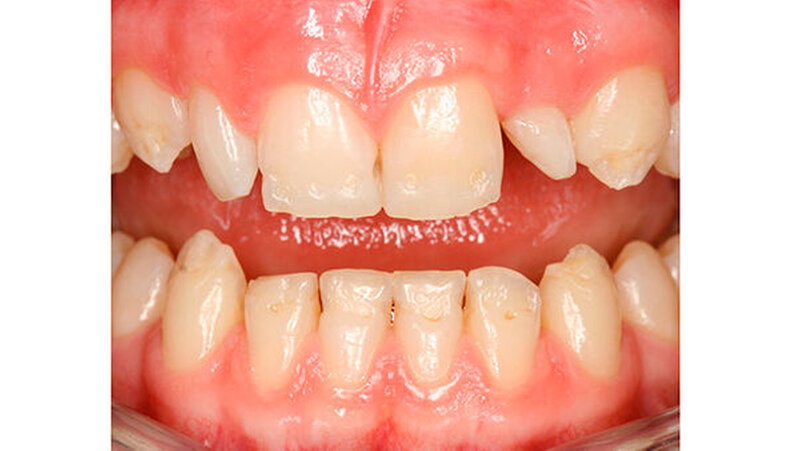

Mit dem Durchbruch der ersten bleibenden Molaren treten dann bisher unbekannte Beschwerden auf wie zum Beispiel eine übermäßig ausgeprägte Kälte-/Wärmeempfindlichkeit. Für manche Kinder wird dadurch nicht nur die Mundhygiene sondern auch die Nahrungsaufnahme erschwert. Zusätzlich bricht oft schon in der Durchbruchs-Phase der Schmelz ein (Abbildung 1), was die Überempfindlichkeit in teils akute Zahnschmerzen übergehen lässt.

Das klinische Bild der MIH reicht von einem bis zu vier betroffenen Molaren, nur selten sind alle Zähne in ähnlicher Ausprägung geschädigt [Weerheijm et al., 2001]. Die bleibenden Frontzähne können ebenfalls betroffen sein, diese weisen allerdings in der Regel keinen Schmelzeinbruch auf und sind selten bis gar nicht überempfindlich [Weerheijm et al., 2001] (Abbildung 2).